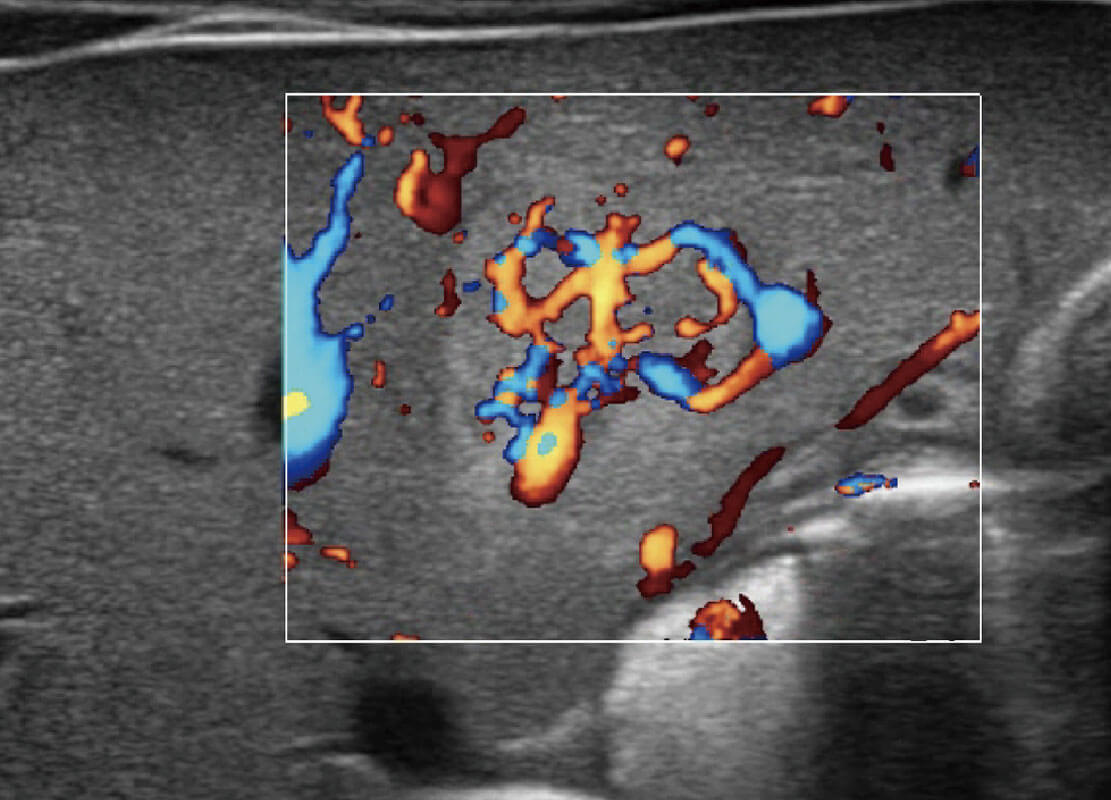

P60搭載寬頻帶線陣探頭、寬景成像、彈性成像技術(shù),為您提供乳腺應(yīng)用方案。P60支持高頻相控陣探頭、線陣探頭、腹部高頻探頭、腹部微凸探頭等,豐富的探頭群搭載敏感的彩色血流成像,適用于新生兒多種臟器檢測要求,滿足新生兒篩查需求。

乳腺癌顯微血流